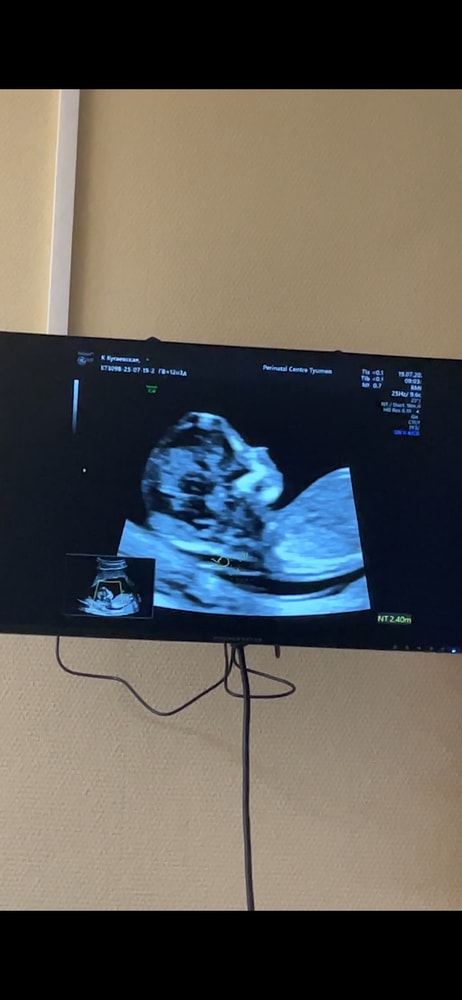

на 1 скрининге на сроке 12.4 недели

ктр 7,1см

Твп 2,8мм

срок по узи 13,2 недели.

все остальные показатели в норме. На узи напугали про твп чуть выше нормы.

Все измерения на фото скринах с узи. Не нашла вообще 2.8

Abigeil, просто странно, три раза намеряла 2,4. Потом один раз 2,7. В итоге написали 2,8